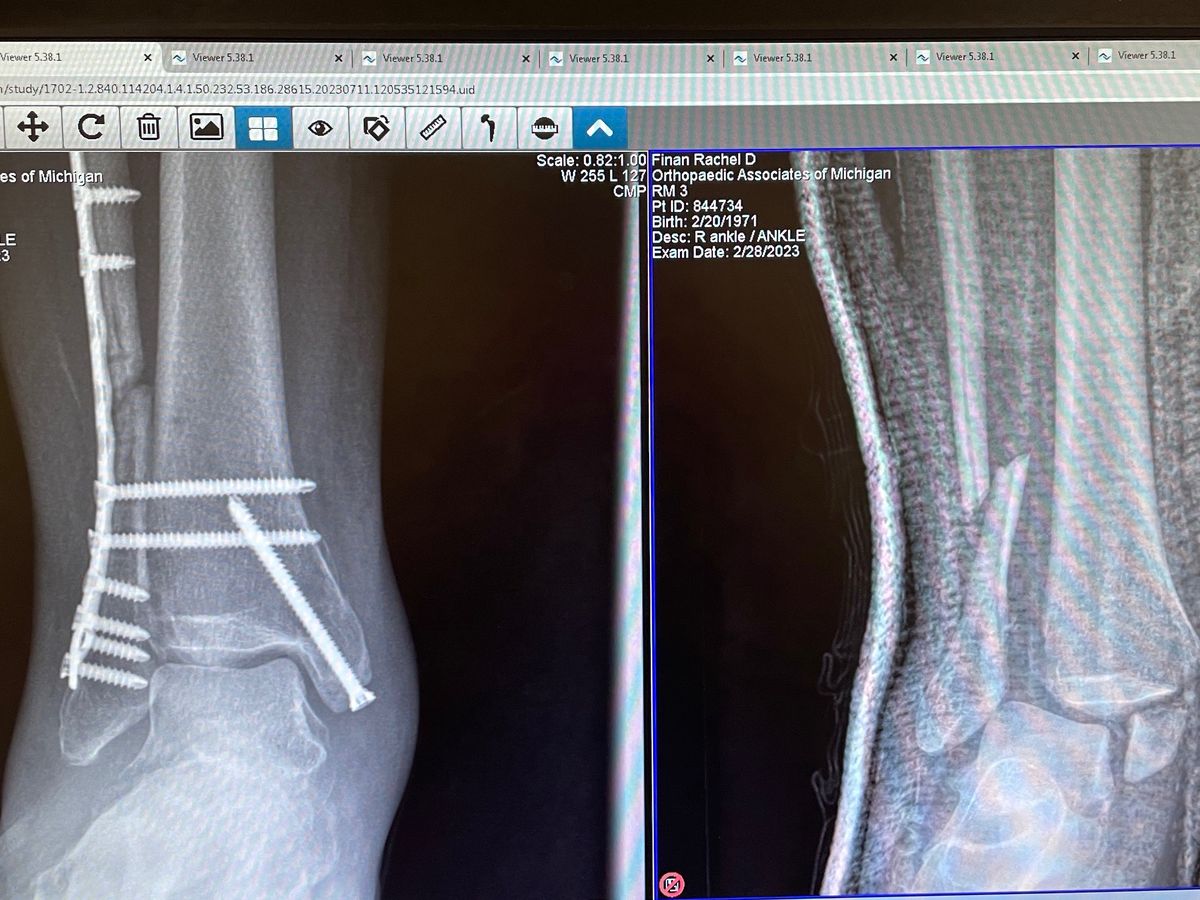

Hey folks, Rachel here. Back in February I shattered my ankle and I have been out of work for the entire time. It is with a heavy heart that I am even creating this fundraiser. I have nearly exhausted my savings just to eat, pay rent and bills. I am at my wits end to say the least. In the last few weeks I’ve been able to work a bit but it’s nothing compared to what my income used to be. I don’t qualify for any kind of government assistance including food stamps or ssdi. I’m reaching out to you all, my friends, family and hopefully fans of Super Happy to help me and my housemate survive these trying times. Please help. I love you all.